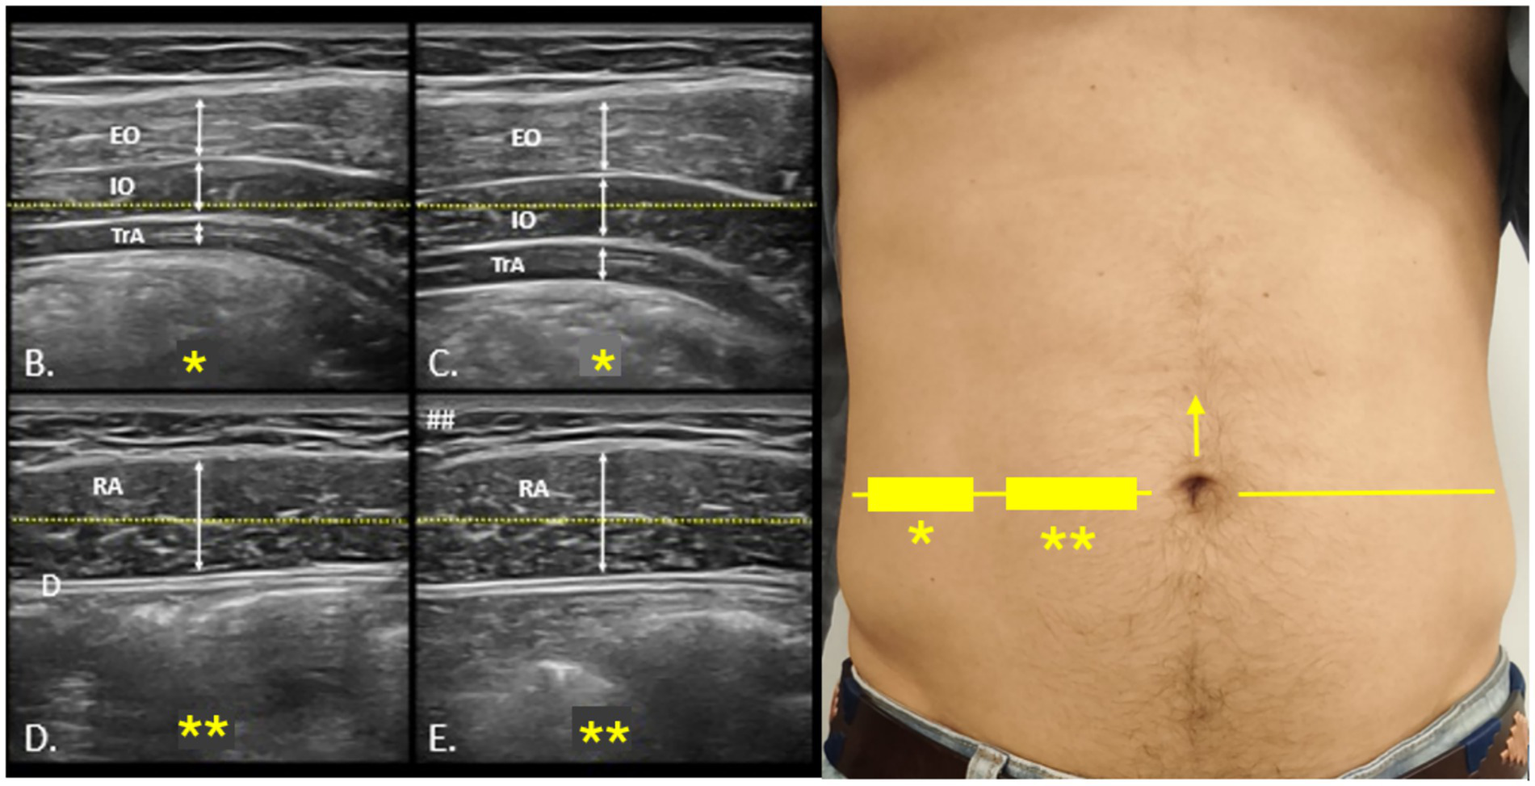

Core muscle morphology was assessed using a portable VSCAN® ultrasound device (GE Healthcare). Participants were positioned supine with comfortable hip and knee flexion. Generous gel was applied to minimize transducer pressure, and a high-frequency linear transducer was oriented transversely at the umbilical zone to visualize external oblique (EO), internal oblique (IO), and transversus abdominis (TA). Images were acquired at relaxed end-expiration when feasible, applying minimal probe pressure. Measurements included the thickness of TA, IO, and EO at rest and during contraction (25). All scans were performed by a single trained examiner following Rehabilitative Ultrasound Imaging (RUSI) standards to minimize measurement bias. For each condition, three measurements were obtained and averaged to ensure accuracy (26–29) (see Figure 2).

Figure 2

Ultrasound protocol for the evaluation of the anterolateral abdominal wall. Probe positioning for ultrasound assessment of the anterolateral abdominal wall (A). The umbilical line, marked with a yellow arrow (→), is used as the reference for locating the lateral abdominal muscles and rectus abdominis, indicated on the skin with rectangles (▭), stars (*), and a horizontal yellow line (—). (B,C) show rest and contraction images of the lateral muscles, while (D,E) illustrate the same conditions for the rectus abdominis. EO, external oblique; IO, internal oblique; TrA, transversus abdominis; RA, rectus abdominis.